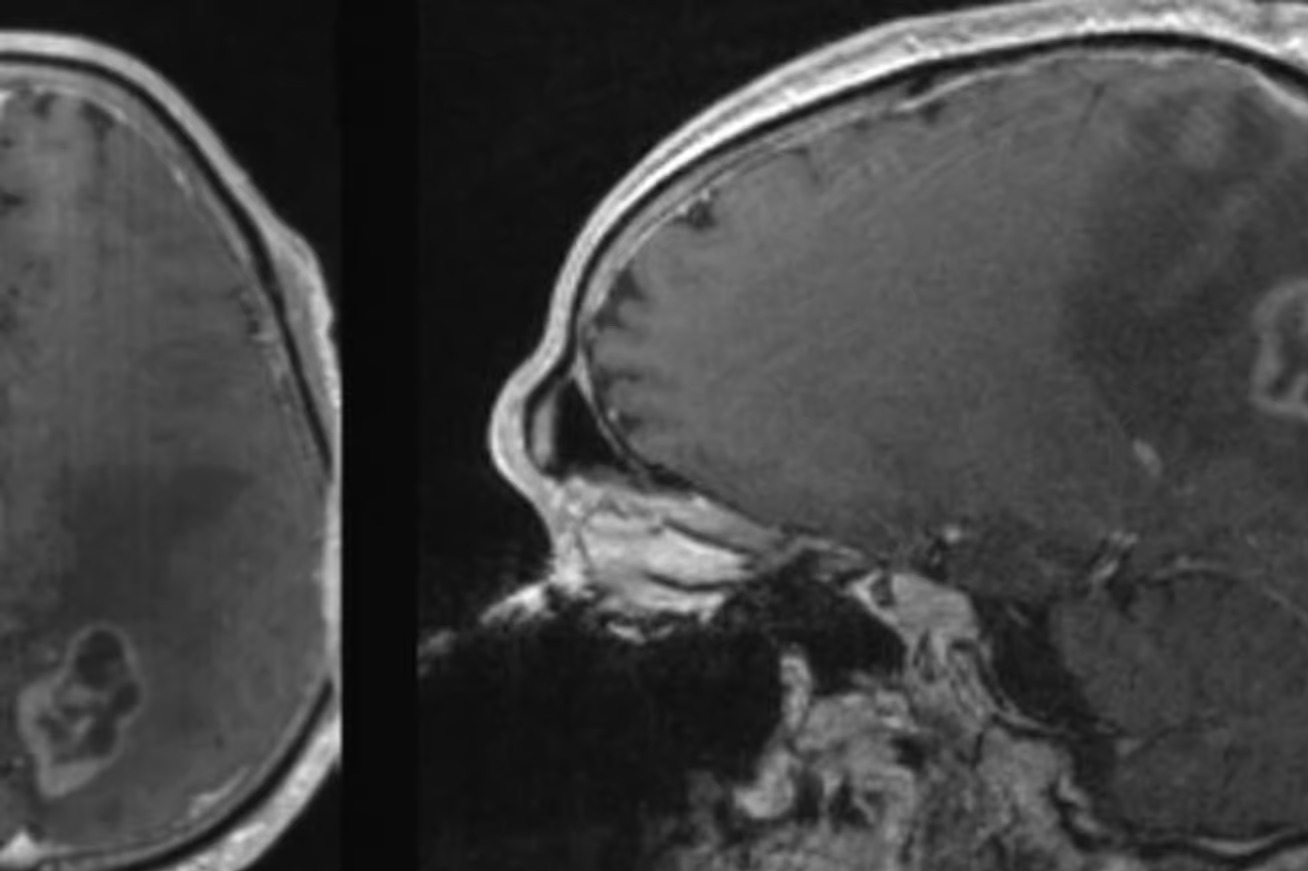

在一项新的研究中,来自北卡罗来纳大学医学院(UNC)和哥伦比亚大学的一个研究小组发现,参与形成胶质母细胞瘤的细胞特别容易受到铁萎缩的影响而死亡。这一发现意义重大,因为胶质母细胞瘤的死亡率为100%,而且没有已知的治疗方法。它也是一种快速发展的癌症,中位生存期只有16个月。

在他们的研究中,研究小组给小鼠喂食了一种限制半胱氨酸和蛋氨酸摄入量的饮食,这两种含硫氨基酸的限制以前与肺癌和胰腺癌以及肉瘤的铁质化和癌细胞死亡有关。他们不仅发现饮食使胶质母细胞瘤细胞更有可能因铁质化而死亡,而且他们还注意到,细胞变得更受化疗药物的影响,这意味着可以用较低的剂量进行治疗。所有接受特殊饮食的小鼠都比接受对照饮食的小鼠的生存期有所改善,而接受联合饮食和化疗方案的小鼠的情况最好。